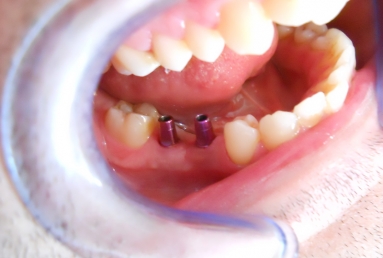

Initial situation: two missing teeth, second lower premolar and first lower molar. two dental implant are integrating in the mandibular bone for 4 months, then, gingival healing caps are applied for 3 weeks. an impression is taken for the dental lab in order to manufacture 2 porcelain fused to metal crowns. they will be screwed directly in the implant body.